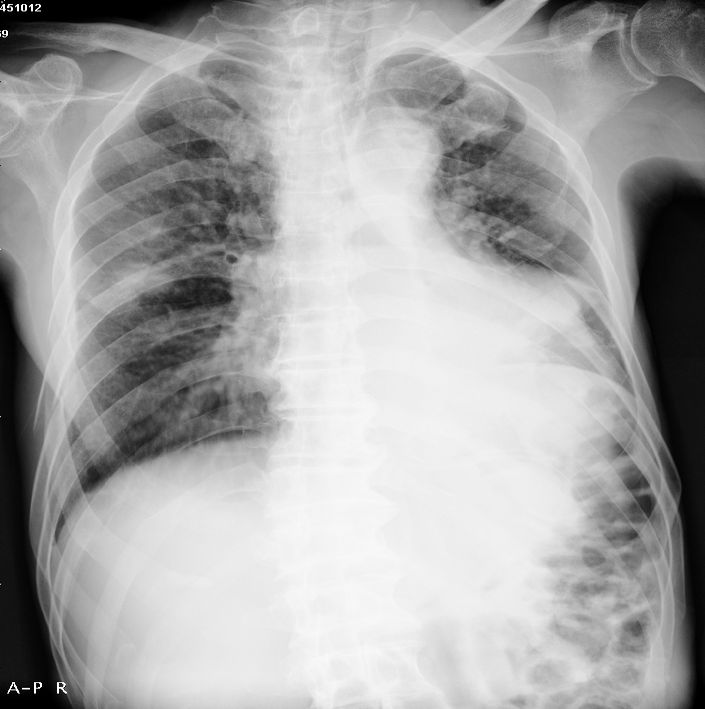

男性,65岁。因外伤来诊。该患者因脑外伤住院。以下是今天的dr和ct:

以下是一周前外伤时的dr: